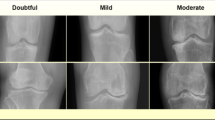

To perform automated phenotyping for knee OA based on radiography, we used a binary classification approach based on the Kellgren-Lawrence (KL) grading system21 (usually graded 0–4, where a 4 is considered the most severe case of radiographic OA) to determine case or control status for each individual reflecting different levels of joint space narrowing, subchondral sclerosis, and the presence of osteophytes. Cases were considered individuals with a KL grade of 3 or higher—severe enough that annotating clinicians would consider a candidate for joint replacement surgery in the clinic. Controls were considered individuals who would not be candidates for joint replacement—a grade 2 or lower (see “Binary classification: DXA scan annotation procedure”). To train the deep-learning model, we obtained case–control assessment on 546 images based on the annotations of three board-certified orthopedic surgeons who independently assessed each image. We then split the dataset so that 80% (436 images) of the data was used for training and 20% (110 images) was used for validation. First, we compared several architectures and found the performance of the ResNet-101 architecture the best for our task (see “Binary classification: model selection” and Fig. 5). We next trained a binary classifier (which we refer to as DL-binary) using transfer learning with the ResNet-101 architecture22 (see “Binary classification: Network architecture and model training” and Figs. 1d, e and 6). The sensitivity and specificity of our model on the validation data (that is not used as part of the training process) was within the range of the sensitivity and specificity obtained between three clinicians grading the same set of images (clinician sensitivity: 0.77 ± 0.05, DL-binary sensitivity: 0.82 ± 0.07 Clinician specificity: 0.97 ± 0.05, DL-binary specificity: 0.95 ± 0.06) (Fig. 1c, d). The DL-binary model achieved an AUROC and AUPRC of 0.96, reflecting the model’s effectiveness in identifying true positives while minimizing false positives (Fig. 1e). We further validated the interpretability of the DL-binary model’s case–control assessment through an additional Grad-CAM analysis (see “Binary classification: Grad-CAM analysis for interpretation of model predictions” and Fig. 7).

Binary classification: DXA scan annotation procedure